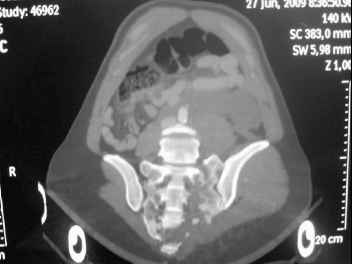

I'm posting this case on behalf of Dr. Pedro Caba, he is unable to post but able to read. 41 yo female , fall from 10 meters five days ago. Hemodynamically unstable on admission treated by angio and embolization and skeletal traction, with no external support. No associated injuries. Based on CT scan the pt has a both column fracture with conminuted dome and displaced anterior column and a sacral Denis 1 fracture with a displaced left ala. I think the best approach for the acetabular fracture is ilioinguinal with Smith-Petersen extension but don't know exactly the sequence . Will you start with the sacral fracture? Which technique? Thanks in advance Pedro Caba Unidad de Trauma Hospital 12 de Octubre Madrid Spain

The soft tissues are also in mild condition, buttock hematoma and probably a Morel-Lavalle. I send some more CT images. There are some conminution in the posterior column (I don’t have images now). The patient is scheduled for surgery next Monday. The plan is percutaneous sacral fixation and then ilioinguinal approach .

This complex and displaced sacral injury is likely an H pattern...2 hemipelvic components, an upper sacral component which remains attached to the lumbar spine, and a caudal sacral component...there are typically anterior ring injuries as well...in this patient's example, the left sided acetabulum also has been exploded.